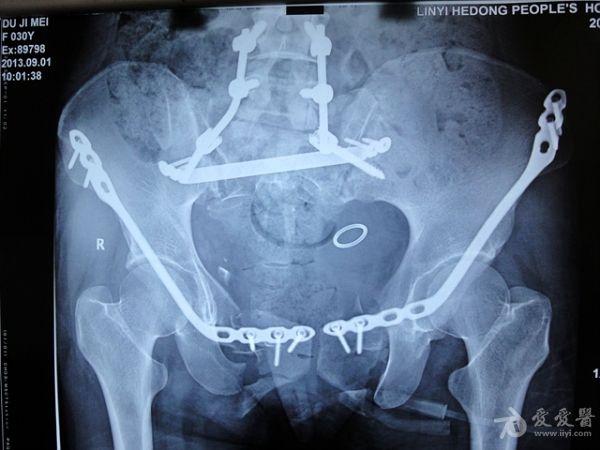

骨盆骨折

小切口解决重大问题,虞城东康医院骨科首例骨盆骨折耻